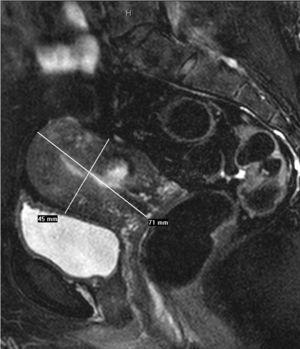

Se realiza RM pélvica (fig. 2B), en la que se visualiza una masa amorfa rodeada de líquido en la cavidad endometrial. A las 24 h, la paciente acude al servicio de urgencias por la expulsión espontánea de un mioma de 7 cm de diámetro con un pedículo muy fino, que se extrajo con facilidad. El resultado anatomopatológico es de mioma necrosado, en el seno del cual aparece material translúcido que corresponde al material de embolización Embosphères® (Biosphère Medical France) (fig. 3).

Figura 2B. Resonancia magnética pélvica (secuencia T1 con contraste sagital). Estudio postembolización. Ocupación por masa amorfa en el interior de la cavidad endometrial con apertura del cuello uterino.